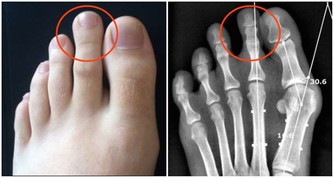

■懶事三:懶得運動,骨質變鬆。

△健康影響:人老了本來就不愛動,加上腿腳不好,很多人會懶得運動,甚至兩三天都不下一次樓。如果長期不運動,人的肌肉會變萎縮,骨關節力量變弱,血液循環減慢,增加骨折、骨關節炎、血栓等風險;不愛動還可能讓老人變胖,而超重和肥胖更會增加「三高」風險,並且,患心腦血管疾病和大腸癌的幾率會增加2~5倍。

△調節方法:經常鍛煉有助預防骨質疏鬆,強健骨骼、肌肉;運動還有益於大腦健康,預防老年癡獃,改善糖尿病、心臟病等多種慢病。

老人鍛煉應動靜結合,鍛煉時感覺不吃力,微微出汗即可;老人還可以多做做家務,哪怕收拾桌子、洗碗這種不費力的小活動,既有益身心,還能美化環境;看書、下棋屬於靜養,可以健腦,但要控製坐著不動的時間,最好半小時就起來走動一下。